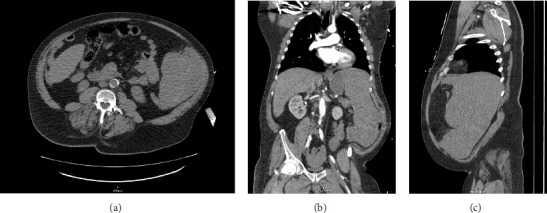

脾破裂导致大出血,需要立即手术治疗。脾破裂是由外伤或潜在疾病引起的。淋巴瘤是一种罕见的非外伤性脾破裂(ASR)的原因,死亡率高。我们报告一例由富含t细胞/组织细胞的大b细胞淋巴瘤(THRLBCL)引起的ASR,需要脾切除术和大容量输血。本病例报告强调了对血液动力学不稳定的ASR及时手术干预和大量输血的必要性。本报告还讨论了大量输血方案(MTP)及其在非创伤性手术患者中的有限应用。

Splenic rupture leads to massive hemorrhage and requires immediate surgical intervention. Splenic rupture results from trauma or from underlying disease processes. Lymphoma is a rare cause of atraumatic splenic rupture (ASR) with high mortality rates. We present a case of ASR due to T-cell/histiocyte-rich large B-cell lymphoma (THRLBCL) requiring splenectomy and large-volume transfusion. This case report highlights the necessity of prompt surgical intervention and massive transfusion for hemodynamically unstable ASR. This report also discusses massive transfusion protocol (MTP) and its limited use in nontraumatic surgical patients.